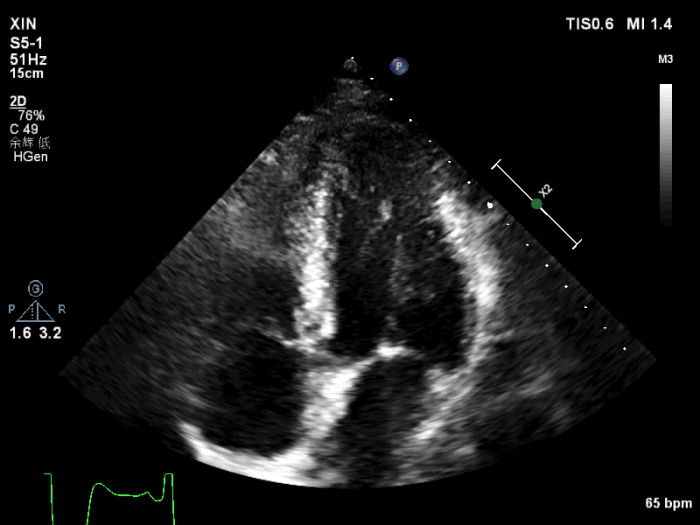

经左心声学造影提示,心尖四腔心:心尖部心肌明显肥厚,呈”黑桃样”改变,心尖部心肌灌注稀少。